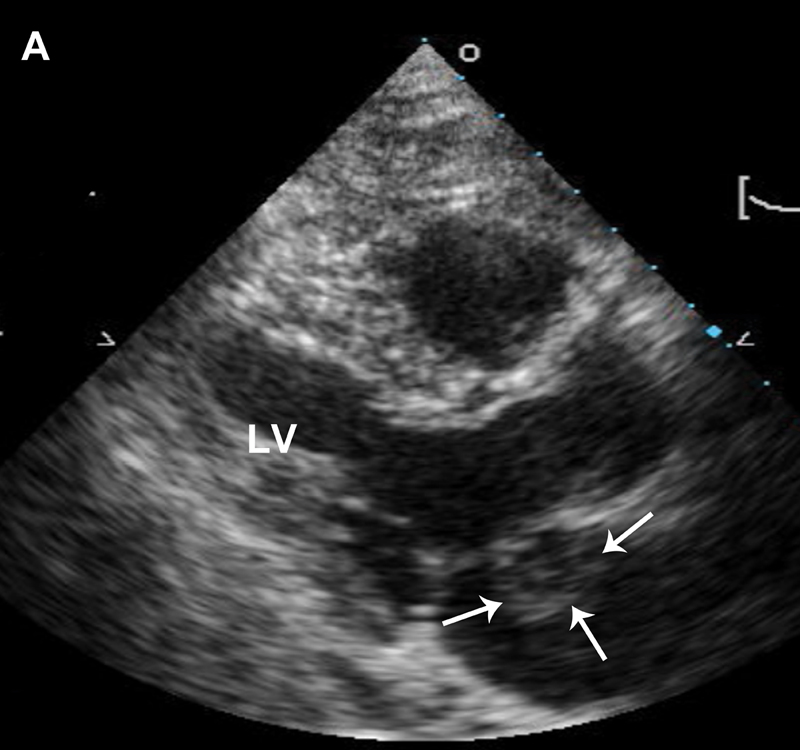

فحوصات تشخيصية لبعض امراض القلب والشرايين التاجية